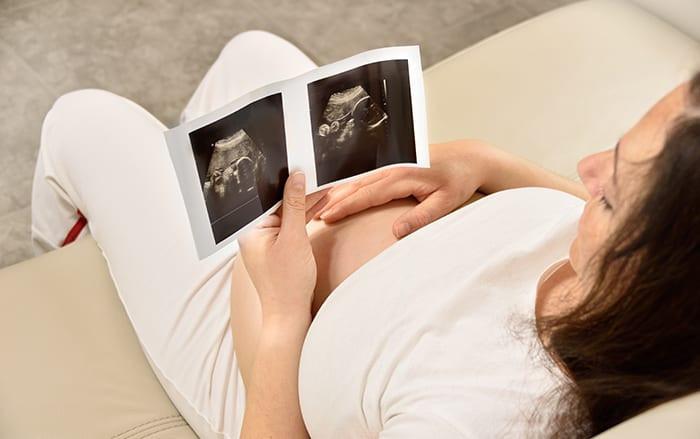

حمل عالي الخطورة (مخاطر الحمل)

يمكن أن يشكل خطورة على صحة الأم والجنين.كيف ممكن ان تعرفي حملك خطر؟

عند الحمل، يوجد دائمًا مخاطر صحية تترافق معه. ولكن يتم تصنيف بعض الحالات على أنها “حمل عالي الخطورة” نظرًا للمخاطر الصحية المتزايدة التي يتعرض لها الجنين أو الأم أو كلاهما.

ومن الممكن أن تحتاج المرأة التي تعاني من الحمل عالي الخطورة إلى رعاية صحية إضافية قبل الولادة وخلالها وبعدها. للمساعدة في تقليل احتمالية حدوث مضاعفات صحية خطيرة. ويمكن أن تشمل هذه الرعاية إجراء فحوصات ومراقبة دقيقة، وعلاجات خاصة. وتوفير بيئة مستشفائية مخصصة لتلبية الاحتياجات الخاصة للأم والجنين.

تشخيص الحمل شديد الخطورة يتم عادةً عن طريق فحص الحالة الصحية للأم والجنين والمراقبة المستمرة لتطور الحمل.

يمكن استخدام فحوصات الدم والبول للكشف عن عيوب خلقية وحالات وراثية، كما يتم استخدام التصوير بالموجات فوق الصوتية لتقييم صحة الجنين ومراقبة حركته وتنفسه ومعدل نموه. يتم أيضًا استخدام مراقبة السائل الأمنيوسي باستخدام الموجات فوق الصوتية واختبار عدم الإجهاد لمراقبة معدل ضربات قلب الجنين وضغط الدم ومستوى الأوكسجين في الدم. قد يتم أيضًا إجراء اختبارات أخرى مثل مراقبة نمو الجنين ومعدل نبضات القلب ومستويات الهرمونات والإنزيمات في الدم.